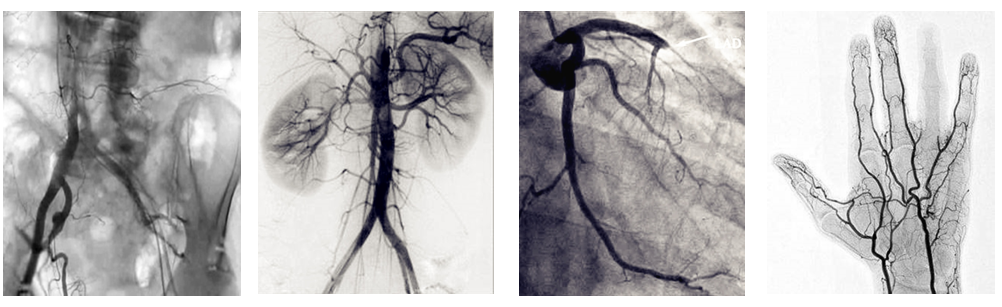

介入c臂機(jī)可以把不需要的組織影像刪除掉,只保留血管影像。圖像清晰,分辨率高,對觀察血管病變,血管狹窄的定位測量,診斷及介入治療提供了真實(shí)的立體圖像,還具有多種工作模式,靈活方便,滿足各種臨床需要,為各種介入治療提供了必備條件。

普愛醫(yī)療PLX7100A數(shù)字移動式C型臂X射線機(jī)是為周邊介入治療而設(shè)計(jì)的移動式平板介入c臂機(jī),配備新型的非晶硅動態(tài)平板探測器,使之成為一款更加貼合介入臨床需求的移動式介入設(shè)備。下面小編給大家介紹下我公司介入c臂機(jī)臨床應(yīng)用及性能特點(diǎn):

PLX7100A移動式介入c臂機(jī),體積小,劑量低,圖像清晰,是廣大基層醫(yī)院介入腫瘤科以及三甲醫(yī)院專科介入(如肝膽外科、ERCP室、婦科)使用的理想設(shè)備。